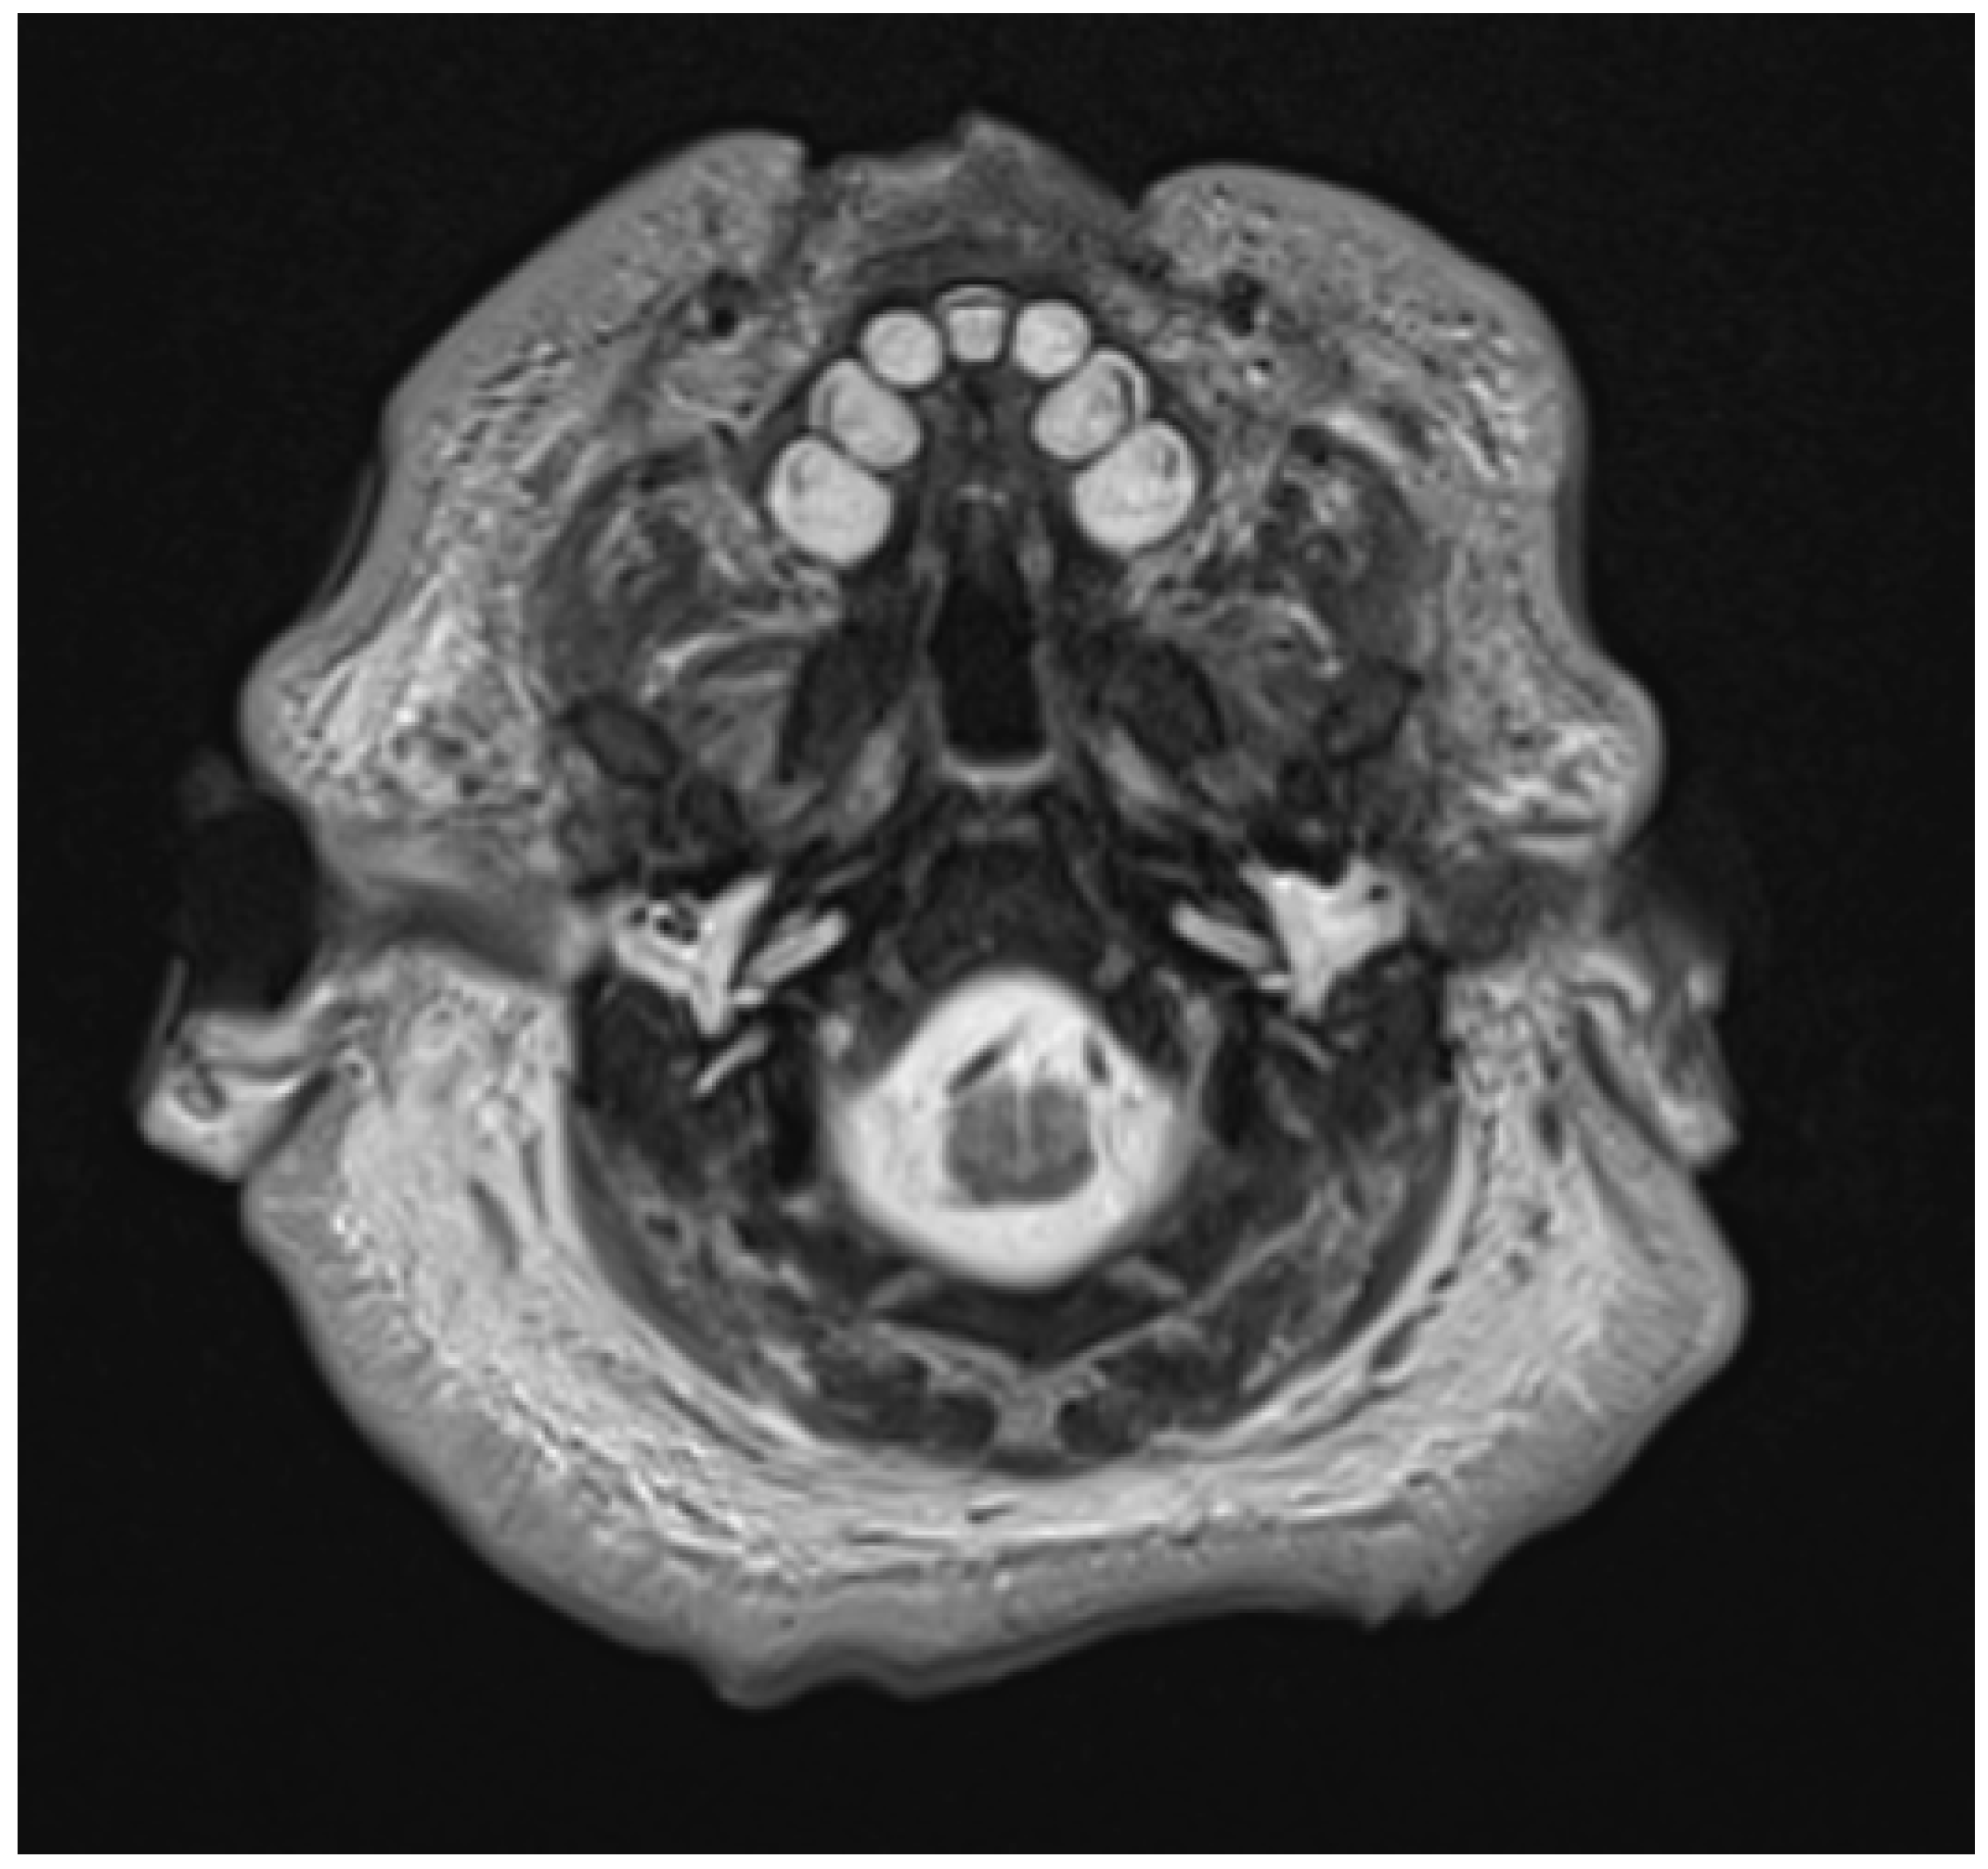

2. Materials and Methods

3. Results

3.3. Radiologic Correlations of Embryological Development

3.4. Application of Principles to Consecutive MR Exams